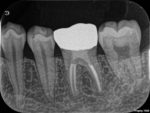

1980年代半ばに、歯冠修復の失敗によって根管充填された根管内に細菌感染が起こることが注目されるようになりました。1995年、RayとTropeによって歯内療法の質と歯冠修復の質が予後に及ぼす影響について大規模な調査が行われました。テンプル大学で治療を行った1010本の根管治療歯のX線写真を調査し、歯内療法の質と歯冠修復の質、根尖部の状態を評価しました。尚、ポストのある歯は除外されました。評価基準は以下のとおりです。

・良い歯内療法(=Good Endo):根管充填材が根管に隙間なく緊密に充填されている。X線上の根尖から0-2.0mm以内に充填されている。

・悪い歯内療法(=Poor Endo):根管充填材と根管の間に隙間がある。根管充填がアンダーかオーバー。